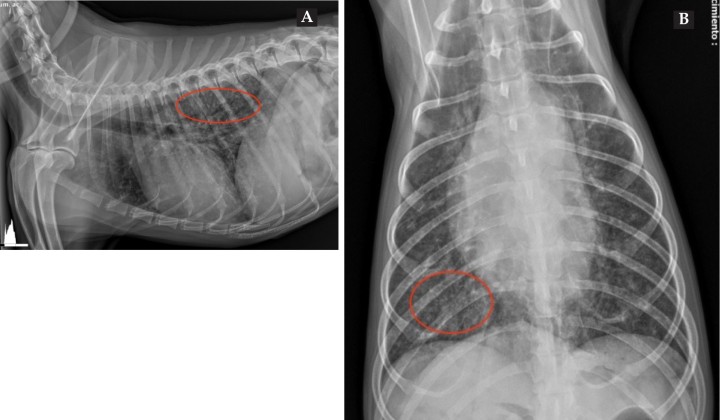

Fueron realizadas radiografías de abdomen en proyección latero-lateral derecha (LL) y ventrodorsal (VD) (Fig. 1), además de un hemograma y una bioquímica sanguínea. Los resultados mostraron una leucocitosis neutrofílica, anemia regenerativa y trombocitopenia, así como elevación de ALT 133 U/l (10-25 U/l), ALKP 220 U/l (23-212 U/l) y TBIL 1,9 mg/dl (0,0-0,9 mg/dl).

<p>Radiografías de abdomen de paciente canino en proyecciones lateral derecha (<strong>A</strong>) y ventrodorsal (<strong>B</strong>).</p>

Radiografías de abdomen de paciente canino en proyecciones lateral derecha (A) y ventrodorsal (B).

Complementamos con radiografías de tórax en proyecciones LL y VD (Fig. 4) que revelaron múltiples nódulos de opacidad tejido blando, menores de 3 mm, afectando mayormente a los lóbulos pulmonares caudales, compatibles con un patrón intersticial estructurado o nodular miliar sugerente de nódulos metastásicos o neumonía granulomatosa fúngica o parasitaria.[ Thrall DE: Canine and feline lung. En Thrall D.E. (7ª ed.): Textbook of Veterinary Diagnostic Radiology, Estados Unidos, Elsevier Saunders, 2018; 710-734. ]

<p>Radiografías lateral derecha (<strong>A</strong>) y ventrodorsal (<strong>B</strong>) con patrón intersticial nodular miliar (círculos rojos).</p>

Radiografías lateral derecha (A) y ventrodorsal (B) con patrón intersticial nodular miliar (círculos rojos).